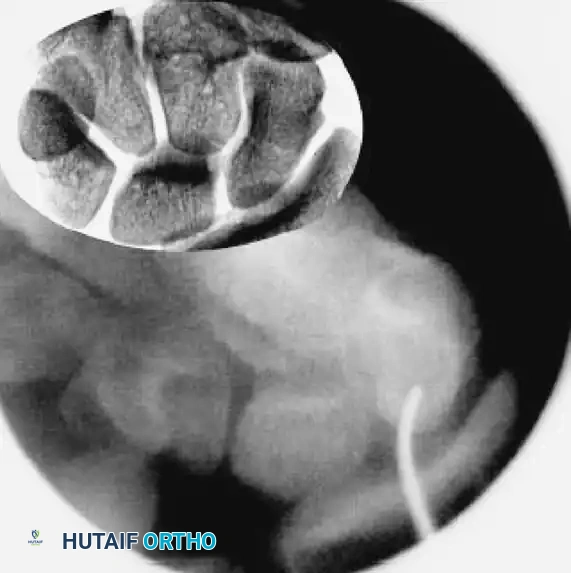

3. Fracture Reduction Techniques (The "Joystick" Method)

If fluoroscopy reveals unsatisfactory fracture reduction, or if dealing with a displaced fracture, percutaneous manipulation is required.

• Insert a 0.062-inch K-wire into the proximal fragment and another into the distal fragment, placing them perpendicular to the axis of the scaphoid.

• Use these stout wires as "joysticks" to toggle and manipulate the fracture fragments into anatomic alignment. If the proximal pole is too small, the proximal joystick can be placed into the lunate to control the proximal carpal row.

• Once aligned, pass the central 0.045-inch guidewire from distal to proximal across the fracture site to capture and hold the reduction.

• Rotational Control: Insert a second 0.045-inch anti-rotation wire parallel to the main guidewire to prevent the fragments from spinning during drilling and screw insertion. Leave the joysticks and anti-rotation wires in place.

Joystick Reduction

FIGURE: Fracture reduction utilizing two 0.062-inch K-wires as "joysticks" to manipulate and align the displaced fracture fragments prior to central guidewire advancement.